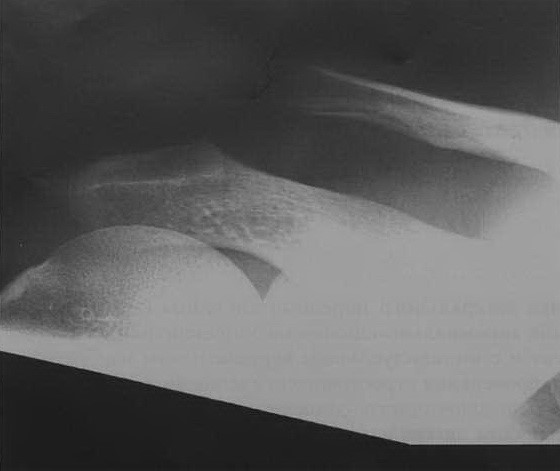

а, b Разрыв левого акромиально-ключичного сочленения (Тосси II). Мужчина 33 лет с болевым синдромом в области акромиально-ключичного сочленения после падения на локоть. Рентгенографическое исследование правого акромиально-ключичного сочленения (а), а также противоположной стороны (b) для сравнения. Расхождение правого акромиально- ключичного сочленения и подъем ключицы на величину около половины ширины диафиза (Тосси II). Величина суставной щели акромиально-ключичного сочленения 1,2 см (норма: не более 0,8 см).

Расхождение акромиально-ключичного сочленения (Тосси III) у мужчины 27 лет после падения с велосипеда. Расхождение акромиально-ключичного сочленения с поднятием уровня ключицы на две ширины диаметра диафиза (Тосси III).